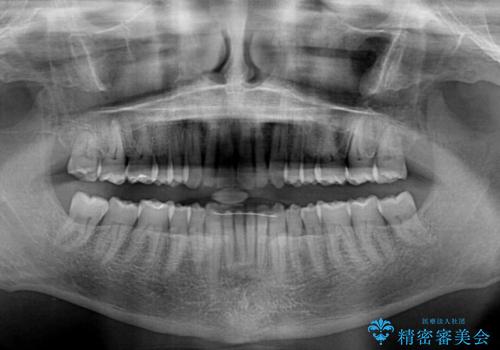

- 前歯のデコボコを気にして来院された患者様です。

インビザラインでもワイヤー装置でも対応可能でしたが、仕事の都合で来院回数を減らしたいとのことでインビザラインによる矯正治療を選択されました。

著しく咬合力が強いため、奥歯がしっかりと噛めずに治療が長引くことが懸念されました。

1セット目のインビザラインを使用した際には左右ともに大臼歯が咬み合っていなかったのですが、2セット目できっちりと仕上げることができました。